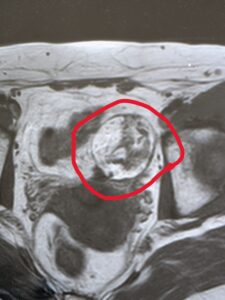

40代の女性です。

全身がんドックDWIBSで見つかった右卵巣腫瘍です。

総合病院にご紹介し、腹腔鏡下卵巣摘出術を行いました。